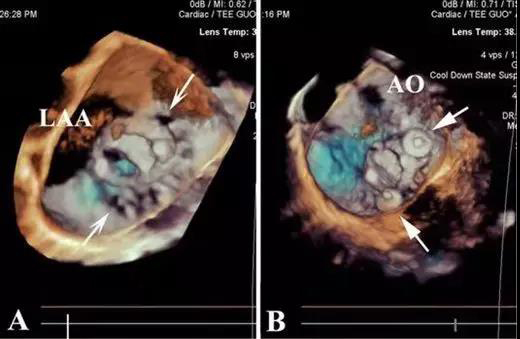

患者杨某,60岁,分别于38年前、18年前做过两次心脏手术, 本次为第三次手术。MPVL呈月牙形,位于11–12点处。由于多次心脏手术心包粘连严重,开胸手术难度大。而月牙形MPVL又是介入治疗的难点,单伞封堵易发生残余漏。他们选取左胸小切口-心尖途径,采用直中空探条引导、双导丝法,植入两枚封堵器,完全堵住了月牙形瓣周漏。患者顺利康复。

经胸MPVL封堵,全部在三维超声引导下操作,解剖图像清晰,患者和医务人员不接触X线和造影剂;中空探条输送系统短,操作灵活,封堵MPVL成功率高。有关该技术的文章已于今年发表于世界顶级心胸外科杂志《Ann Thorac Surg》上。三位患者的成功表明:经右胸或左胸途径微创封堵MPVL能克服传统介入治疗的不同难点,已逐步走向成熟,成为治疗二尖瓣瓣周漏的又一利器,为患者解除了再手术痛苦,为心外科医生解除了后顾之忧。